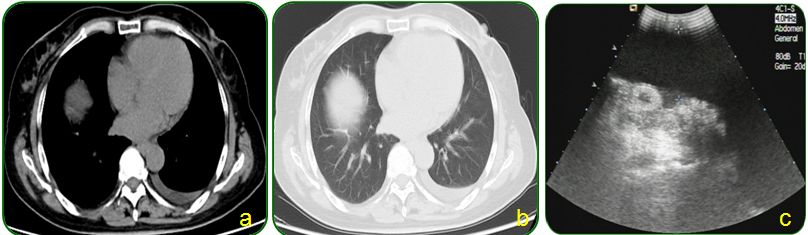

肺部及腹部CT提示右侧胸腔大量积液,右肺中下叶局限性膨胀不全、左肺上叶前段小结节影、纵隔稍肿大淋巴结、腹腔大量积液、盆腔少量积液、肝胆脾、胰腺及双肾CT平扫未见明显异常征象,如图5;

图5 胸部及腹部CT检查

基本该患者诊断结核感染,那到底是肺结核还是结核性腹膜炎,我们还需要进一步了解。肺部CT提示右侧胸腔大量积液,右肺中下叶局限性膨胀不全,右侧不能排除有无结核病灶,大量胸水可干扰观察,一般建议胸腔穿刺后复查肺部CT或胸片;如果不是肺结核,结核性腹膜炎会导致这样大量胸水吗?答案是肯定的,结核性腹膜炎导致腹腔大量积液很好理解,但腹腔大量腹腔积液也可以导致胸水。